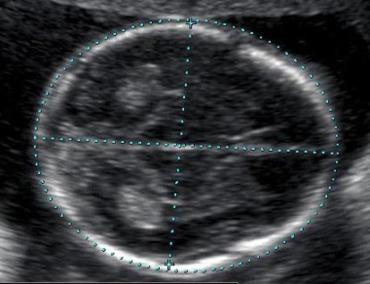

УЗИ головы новорожденного проводят посредством нейросонографии. С его помощью диагностируют новорожденного грудничка и малыша до года. В редких случаях, если у него не зарос родничок, проводится до полутора лет включительно. При помощи высокочастотных волн изображение формируется на экране. УЗИ головного мозга новорожденных отличается безболезненностью и безопасностью.

Под нейрофизиографией подразумевается проведение ультразвукового обследования мозга у новорожденных и малышей до 1 года. Высокочастотные колебания отражаются от мозга и отображают его очертания на цифровом дисплее.

Процедура длится максимум 15 минут. Для обследования головы специалист закрепляет сенсоры на переднем родничке и в области висков. В редких примерах обследуются затылочные участки. УЗИ проводится для того, чтобы получить достоверные сведения о состоянии головного мозга новорожденного.

Нейросонография головного мозга новорожденных делается чаще всего через родничок малыша. Это область расположена между лобной, а также теменной костью. Помимо переднего родничка, УЗИ могут делать через особое затылочное отверстие головы ребёнка и небольшие боковые височные роднички.

Перед процедурой, ребёнка кладут на кушетку, постелив перед этим на неё пелёнку. При процедуре, мама имеет право присутствовать и придерживать голову ребёнка в случае необходимости. На датчик наносится специальный гель, после чего, врач водит им по голове ребёнка. В это время, импульсы, которые принимает аппарат, выводится на экран в форме движущейся картинки.

Во время проведения УЗИ, врач обращает своё внимание на мозговые желудочки, полости прозрачной перегородки, а также цистерны. Осмотр цистерны для врача имеет очень большое значение. Связано это с тем, что её состояние показывает нарушения в развитии задней ямки черепа.

Исследование длиться не более 10 мин. По окончании обследования, голову ребёнка следует аккуратно протереть тканью, чтобы убрать остатки крема. Результаты нейросонографии будут готовы после нескольких минут.

Как проводится исследование

Применение УЗИ головного мозга новорожденного не требует какой-либо специальной подготовки. Единственным и важным условием является спокойное поведение малыша. Поэтому обследуют младенцев в основном во время сна или сразу после еды. В общей сложности исследование занимает не более 15 минут.Для исследования головы врач прикладывает ультразвуковой датчик к переднему родничку и к височным областям. В редких случаях используют затылочные участки. Получить достоверные замеры – главная цель использования УЗИ головного мозга новорожденного. Норма этих показателей служит эталоном для сравнения и выявления каких-либо отклонений. Всего используют двенадцать стандартных показателей. Потом сверяются полученные данные с нормальными значениями, и выявляется диагноз. По результатам обследования в случае выявления патологий невролог назначает лечение.

Как проводят у новорожденных

Нейросонография (иначе этот метод называют эхоэнцефалографией) позволяет быстро и абсолютно безболезненно выявить эти и целый ряд других диагнозов и своевременно принять меры по излечению малютки. Малыша просто укладывают на кушетку, закрепляют на головке датчики: на височные области и основной (большой) родничок на темени, иногда устанавливают датчик и на затылочную часть. Все они предварительно смазываются специальным гелем.

На экране дисплея специалист видит объективную картину состояния тканей мозга, проводит сонометрию, то есть осуществляет все требуемые замеры, обращая внимание на все несоответствия с показателями нормы. Через 10 минут врач-исследователь может заняться уже расшифровкой полученных данных, которые потом помогут лечащему врачу с постановкой диагноза. Если потребуются некие уточняющие детали, доктор даст направление на МРТ или КТ.